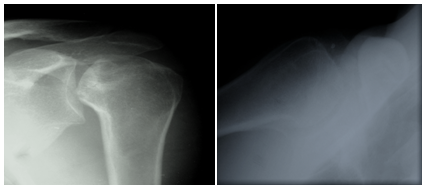

Figure 6 Pre- operative four part fracture dislocation.

Figure 7 Immediate postoperative films showing congruous reduction, stabilized greater tuberosity and contained head of humerus.

Figure 8 6 months postoperative films-good contained head of humerus, no signs of avascular necrosis and patient had excellent shoulder function.